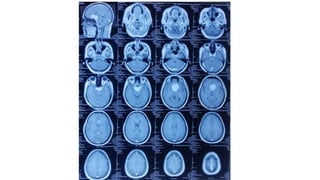

Radiological findings

• Multiplaner sagital ,coronal and axial images show a well defined ,midline, broad dural based,

lobulated T1WI iso , T2WI iso to slightly hyper and FlAIR hyperintense mass noted in suprasellar

Radiological findings • Multiplanersagital ,coronal and axial images show a well defined ,midline, broad dural based, lobulated T1WI iso , T2WI iso to slightly hyper and FlAIR hyperintense mass noted in suprasellar area having extension forwards along the planum sphenoidale and backwards along the dorsum sellae. • After IV contrast avidly homogenous enhancement of the lesion and adjacent linear dural enhancement over the clivus and planum sphenoidale representing dural tail are noted. • The lesion causing compression over the optic chiasma, pituitary gland and floor of 3rd ventricle, and encasing the supraclinoid ICA, ACA and MCA of both sides. • The mass effect is evidenced by obliteration of Suprasellar & interpeduncular cysterns and symmetrical indentation of underlying cerebral cortex. • No perilsional edema is noted • However lateral , 3rd and 4rth ventricles appear normal • Complementary CT cut was taken and showing iso to slightly hyperdense lesion. No calcification is noted. Bone CT shows bony hyperostosis at planum sphenoidale .Sellar size is within normal limit

Radiological diagnosis • Suprasellarmeningioma with planum sphenonale and dorsum sallar extension